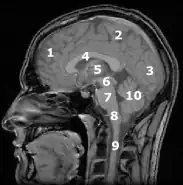

Mózgowie człowieka

Mózgowie (łac. encephalon z gr. en „w, wewnątrz” i kephalos „głowa”) – część ośrodkowego układu nerwowego leżąca w czaszce. Jest to najbardziej złożony narząd człowieka. Stopień jego rozwoju prawdopodobnie warunkuje istnienie świadomości. Między neuronami czuciowymi i ruchowymi rozmieszczone są włókna kojarzeniowe.

Podział mózgowia

Podział topograficzny

W tym podziale części składowe mózgowia stanowią pierwotne pęcherzyki mózgowe zarodka (przodomózgowie, śródmózgowie i tyłomózgowie) dzielące się dalej na wtórne pęcherzyki mózgowe. Jedynie śródmózgowie nie ulega podziałowi na wtórne pęcherzyki.

Anatomia i fizjologia

Jamki zarodkowych pęcherzyków mózgu utrzymują się przez cały czas kształtowania się mózgu tworząc w wykształconym już mózgu komory mózgowe, które wypełnione są surowiczym płynem mózgowo-rdzeniowym. Z bocznych pęcherzykowatych wypukleń mózgu pierwotnego wytwarzają się oczy; z przodu tworzy się płat węchowy. Im wyżej na filogenetycznej drabinie stoją kręgowce, tym znaczniejszy obserwuje się rozwój przodomózgowia, które w końcu tworzy właściwy mózg (cerebrum), składający się z dwóch półkul (prawej i lewej). U człowieka przykrywają one całą resztę mózgu.

Półkule te są pofałdowane, co znacznie zwiększa ich powierzchnię. Wyróżnia się na nich bruzdy (sulci, fissurae) i zakręty (gyri). Półkule mózgowe rozwijają się kosztem międzymózgowia i śródmózgowia. Z tyłomózgowia powstaje móżdżek, a rdzeniomózgowie zamienia się w rdzeń przedłużony. Masa mózgu ludzkiego wynosi u mężczyzny około 1375 g, u kobiety 1225 g, podczas gdy masa mózgu niemowlęcia to zwykle około 350 g. Obydwie półkule rozdzielone są głęboką bruzdą podłużną, a tylko w dolnej części złączone są wielkim spoidłem mózgowym, ze śródmózgowiem natomiast łączą się za pomocą szypułek mózgowych (pedunculi cerebri). Głęboka bruzda boczna, zwana bruzdą Sylwiusza[1], przecina pod spodem półkule mózgowe, tak że dzieli każdą półkulę (od spodu) na 5 płatów:

Płat ciemieniowy przechodzi bez ostrej granicy w płat potyliczny. Wąska jama obecna w półkulach mózgowych podzielona jest przez ścianę podłużną na dwie równe części – w ten sposób powstają komory boczne mózgu (ventriculi cereibri). Tylna część tej ściany tzw. sklepienie mózgu wychodzi z ciał suteczkowatych, znajdujących się u podstawy mózgu. Komory boczne i komora trzecia (w międzymózgowiu) komunikują się ze sobą przez ciasny otwór Monroe’go (foramen Monroi). Przedłużenia bocznych komór noszą nazwę rogów Ammona (cornu ammonis). Półkule mózgowe zbudowane są z istoty szarej (zwanej korą mózgową), o miąższości około 5 mm, obfitującej w komórki zwojowe, i z białej istoty rdzennej złożonej z włókien nerwowych. Dno komory trzeciej mieszczącej się w międzymózgowiu przedłuża się ku dołowi w lejek, na którym położona jest przysadka mózgowa, gruczoł wydzielania wewnętrznego. Z międzymózgowia wychodzi również, jednak ku górze, szyszynka.